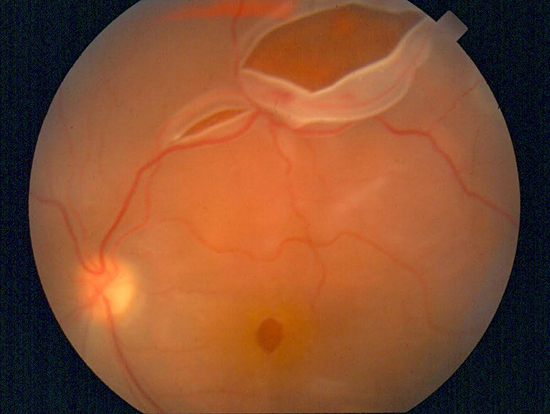

Myopia by itself reduces the quality of life but the main problem is the resulting complications, leading to blindness and low vision (retinal detachment and myopic maculopathy).

Retinal detachment

Myopic maculopathy